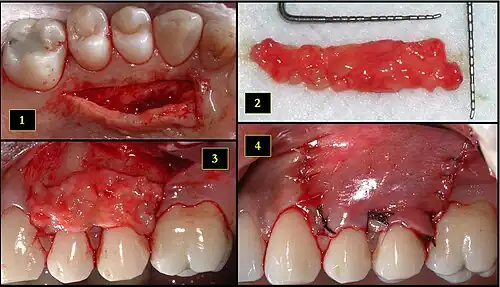

Subepithelial connective tissue graft

- Recipient site exhibits gingival recession on both premolars and first molar (molar recession is not an esthetic issue and will not be treated)

- Incisions prior to flap reflection

- Full thickness flap elevated

- Another viewpoint of the flapped recipient site